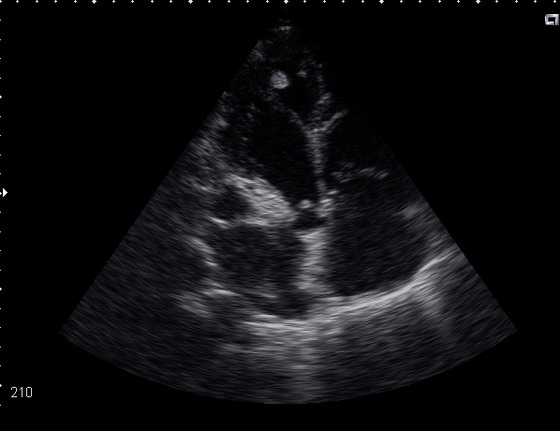

ЭхоКГ: ПЖ-40см, ЛЖ КДР -65,КДО-178мл, КСО-121мл, МЖП сис.11см\ диаст.12, ЗСЛЖ сис 11\13, ФВ- 32%, давление в легочной артерии 14ммHg, умеренная дилтация ЛП и ПП ( регургитация митральная 1 ст. трикуспидальная 2ст).

В области верхушки левого желудочка лоцируются 2 округлых образования одно из котрых находится на дополнительной хорде. Есть мнение, что это внеклапанный бак.эндокардит, а есть, что это миокардит с тромбом верхушки ЛЖ. Ваше мнение?

Внешне структуры в области верхушки мало похожи на тромб. Можно попробовать рассмотреть эту зону с помощью конвекса с бОльшей частотой сканирования. В целом, клиническая оценка состояния пациента может быть более полезной для диагноза, чем гадания по УЗ-картинке.

Сегодня у больного развилась клиника инфаркта мозга. При ЭхоКГ в области верхушки никаких дополнительных структур не обнаружено.

Учитывая клинику, лабораторные данные (не было ни лейкоцитоза, ни высокого СОЭ, а бакэндокардит-это всё же септическое состояние, и кстати, в последнем анализе СОЭ было 0.5мм\ч) думаю вероятнее это был тромб.

Описанная ЭХО-картина в большей степени соответствует ДКМП, чем инфекционному эндокардиту. А для ДКМП (или если хотите миокардита Абрамова - Фидлера) характерно пристеночное тромбообразование. А тем более на фоне фибрилляции предсердий